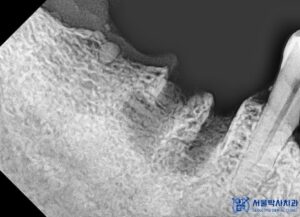

만약 임플란트를 잘못된 각도로 식립하게 되면,

음식물이 자주 끼거나, 잇몸과 임플란트 사이에

틈이 생겨 염증이 반복될 수 있고,

결국 임플란트 주위염으로 인해 임플란트를

다시 제거해야 할 수도 있습니다.

또 씹는 힘이 제대로 전달되지 않아 불편함을 느끼거나,

심한 경우 보철물이 파절되는 경우도 있습니다.

이러한 문제를 예방하기 위해서는 숙련된 술자의

경험과 더불어 정확한 진단과 계획,

그리고 정밀한 식립이 필수입니다.